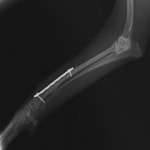

ペルシャ猫 11ヶ月齢 雄

他院にて左大腿骨遠位の成長板骨折(salter-harrisⅠ型)が認められており、治療相談を目的として来院。当院にて、キルシュナーワイヤーを用いたピンニングにより骨折部位の整復を行いました。術後の経過は良好で、現在も経過観察中です。

術前レントゲン

術後レントゲン

Arthrex社のターゲティングデバイスを用いてピンニングの位置を調整することで、確実な固定を行っています。当院ではこの手術器具以外にも、人の手術にも使用される様々な器具を導入し、手術精度を高め、また医療メーカーと新しい器具の開発、試作にも取り組んでおります。